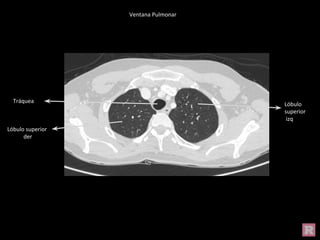

Ventana Pulmonar

Tráquea

Lóbulo superior

izq

Lóbulo superior der